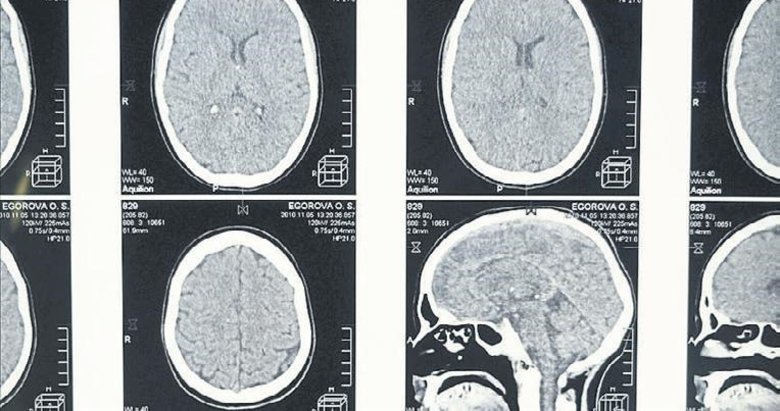

Bilim insanları, uykunun REM (hızlı göz hareketi) evresine geçmekte zorlanmanın Alzheimer belirtisi olabileceğini tespit etti. Science Daily'nin haberine göre araştırmacılar, yaş ortalaması 70 olan ve yarısına daha önceden Alzheimer teşhisi konulmuş 128 kişiyi klinikte uyutarak gözlemledi. REM evresine ulaşanlar "erken", yaklaşık 193 dakikadan daha uzun sürede geçenler ise "geç" grup olarak sınıflandırdı. Çalışma sonucunda, uykunun REM evresine "geç" ulaşan kişilere, daha önce Alzheimer hastalığı tanısı konmuş olma ihtimalinin daha yüksek olduğu tespit edildi.